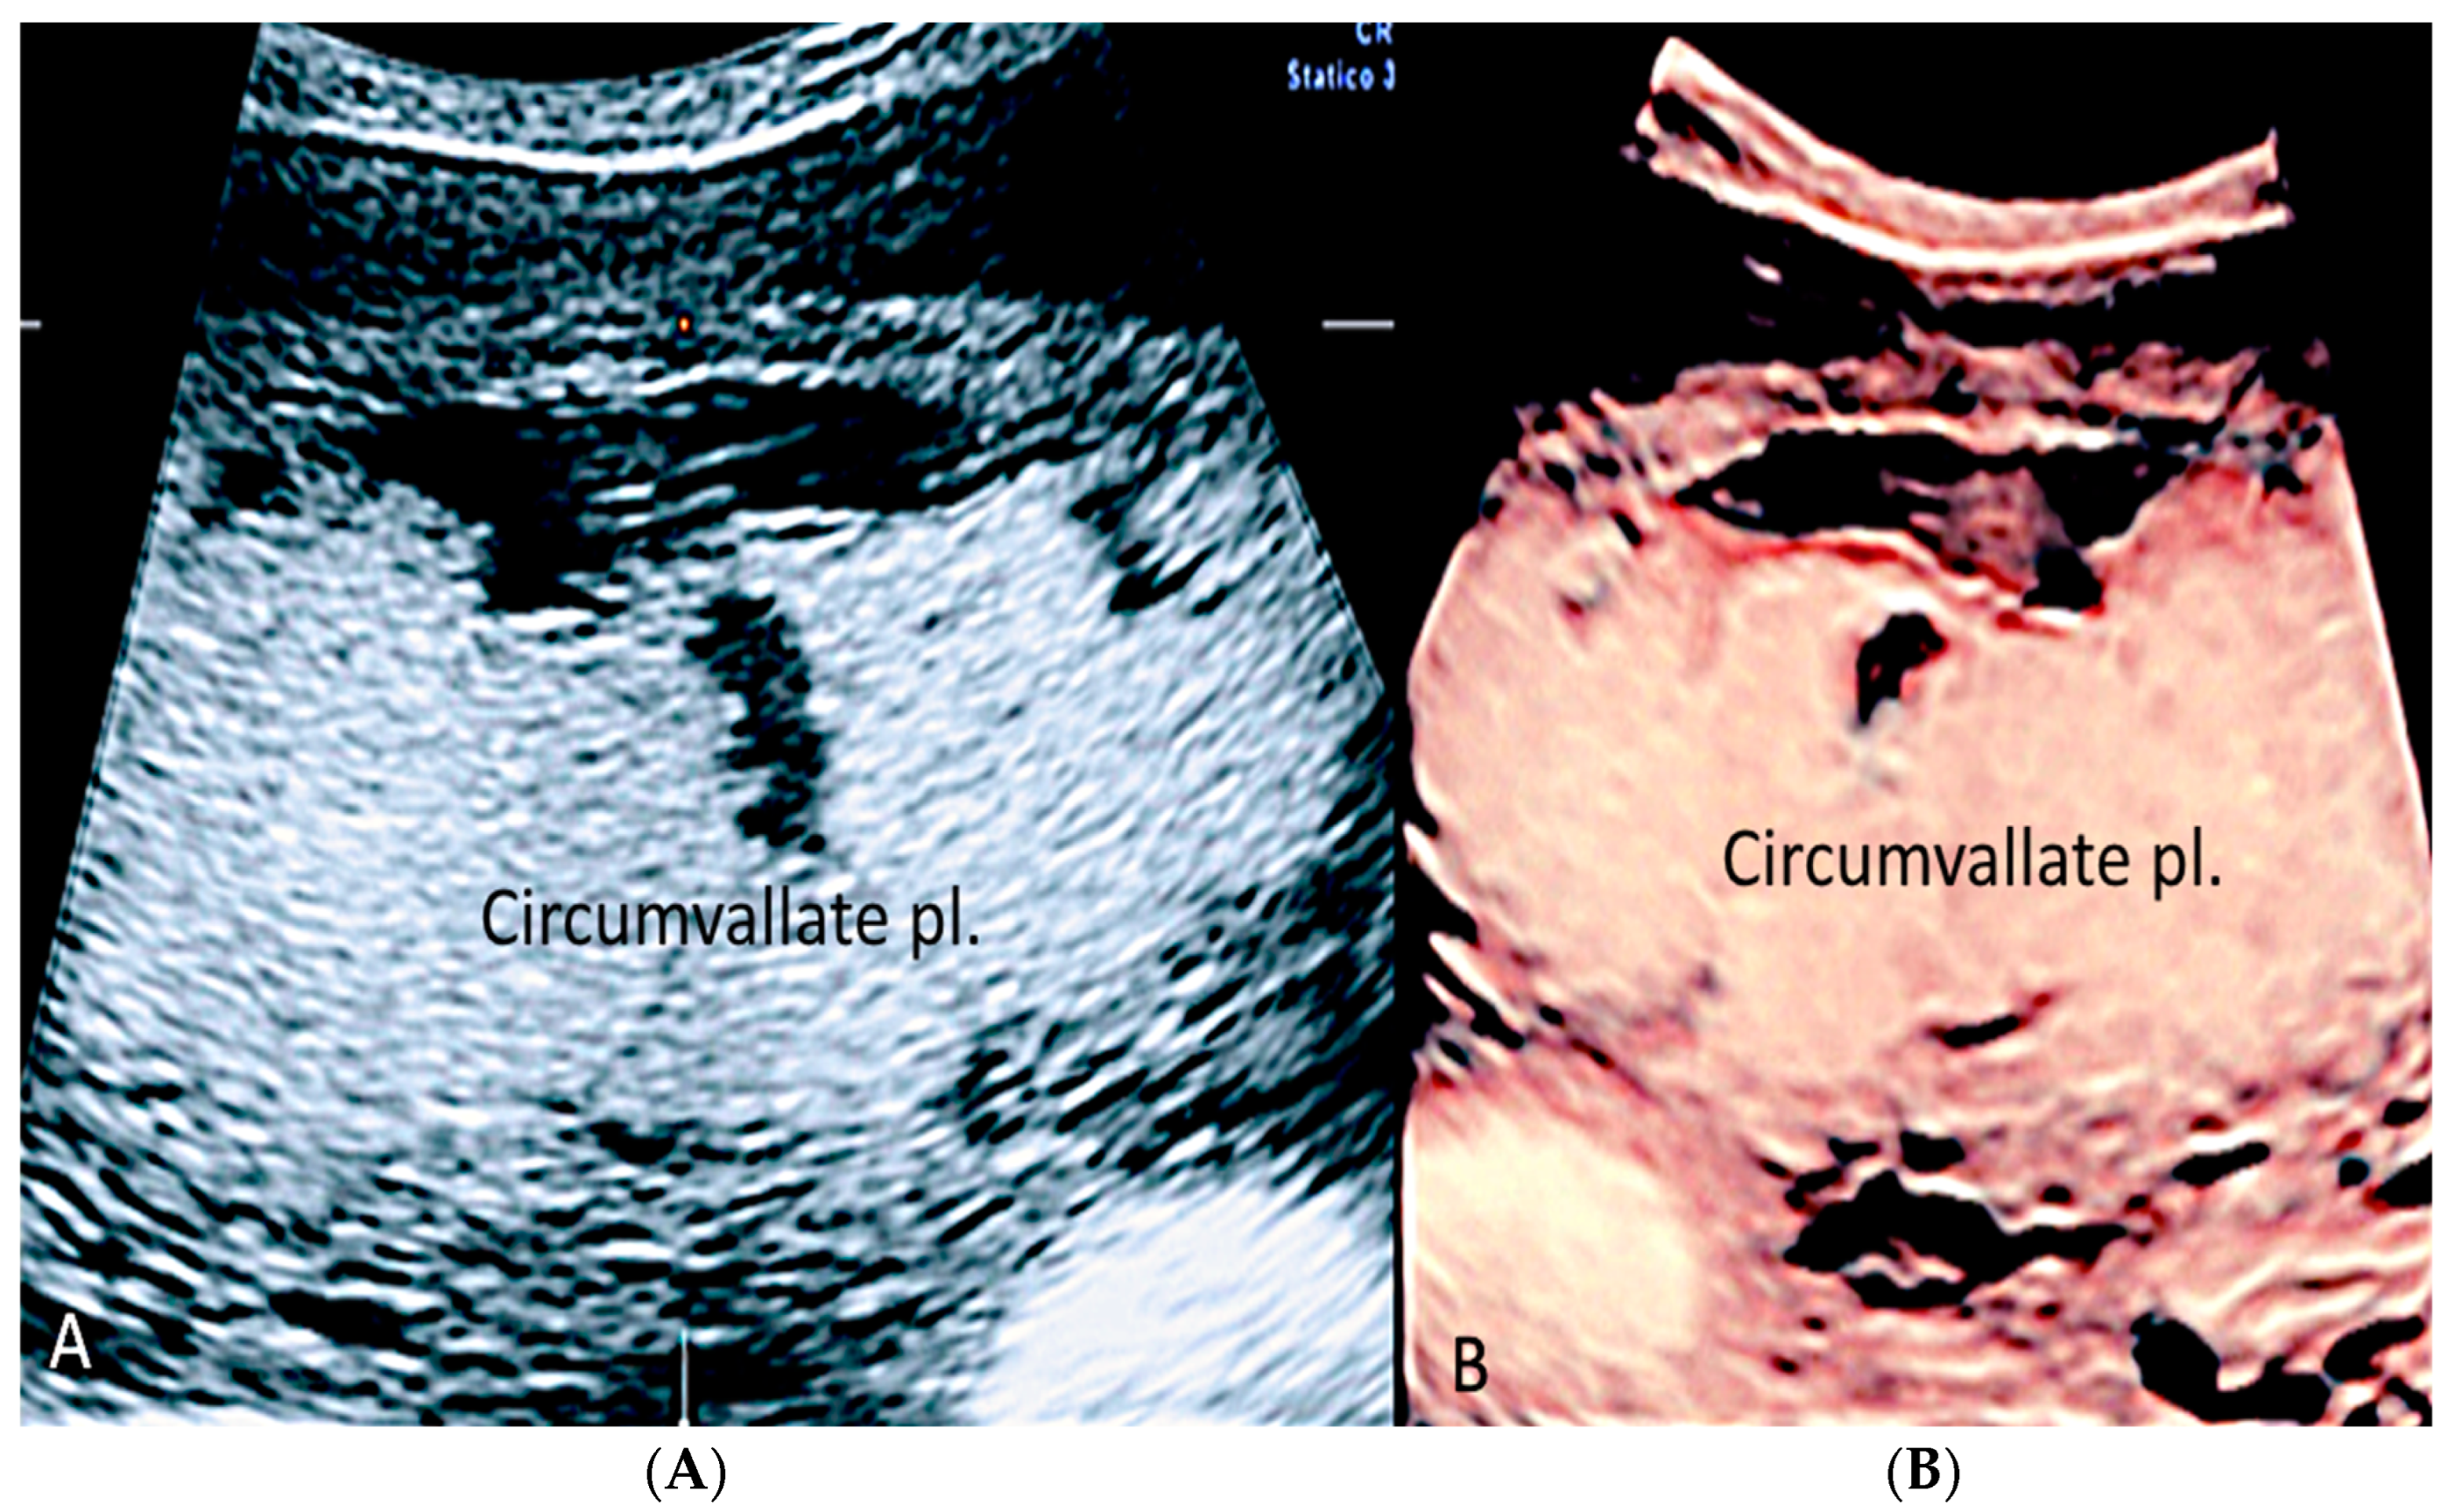

3.1.4. Circumvallate Placenta

- Arlicot, C.; Herve, P.; Simon, E.; Perrotin, F. Three-dimensional surface rendering of the chorionic placental plate: The “Tire” Sign for the diagnosis of a circumvallate placenta. J. Ultrasound Med. 2012, 31, 337–341. [Google Scholar] [CrossRef]

- Suzuki, S. Antenatal screening for circumvallate placenta. J. Med. Ultrason. 2008, 35, 71–73. [Google Scholar] [CrossRef] [PubMed]